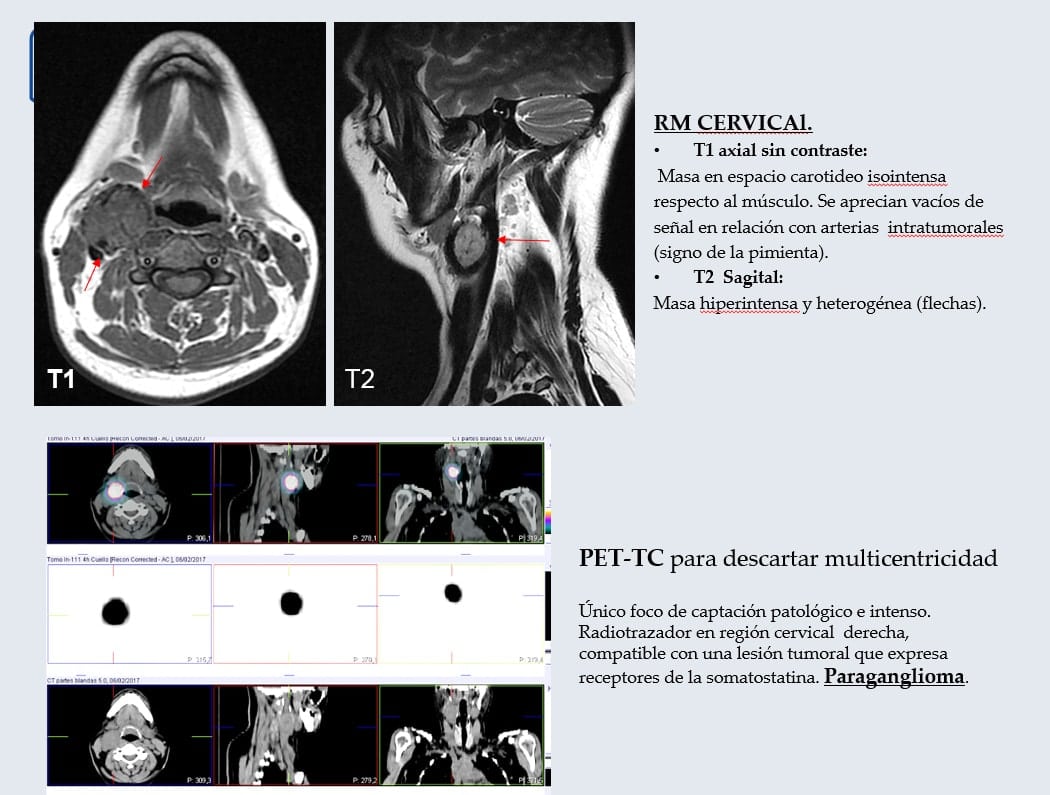

Correlación Histopatológica de Glomus Carotídeo tratado con Onyx y posteriormente resecado